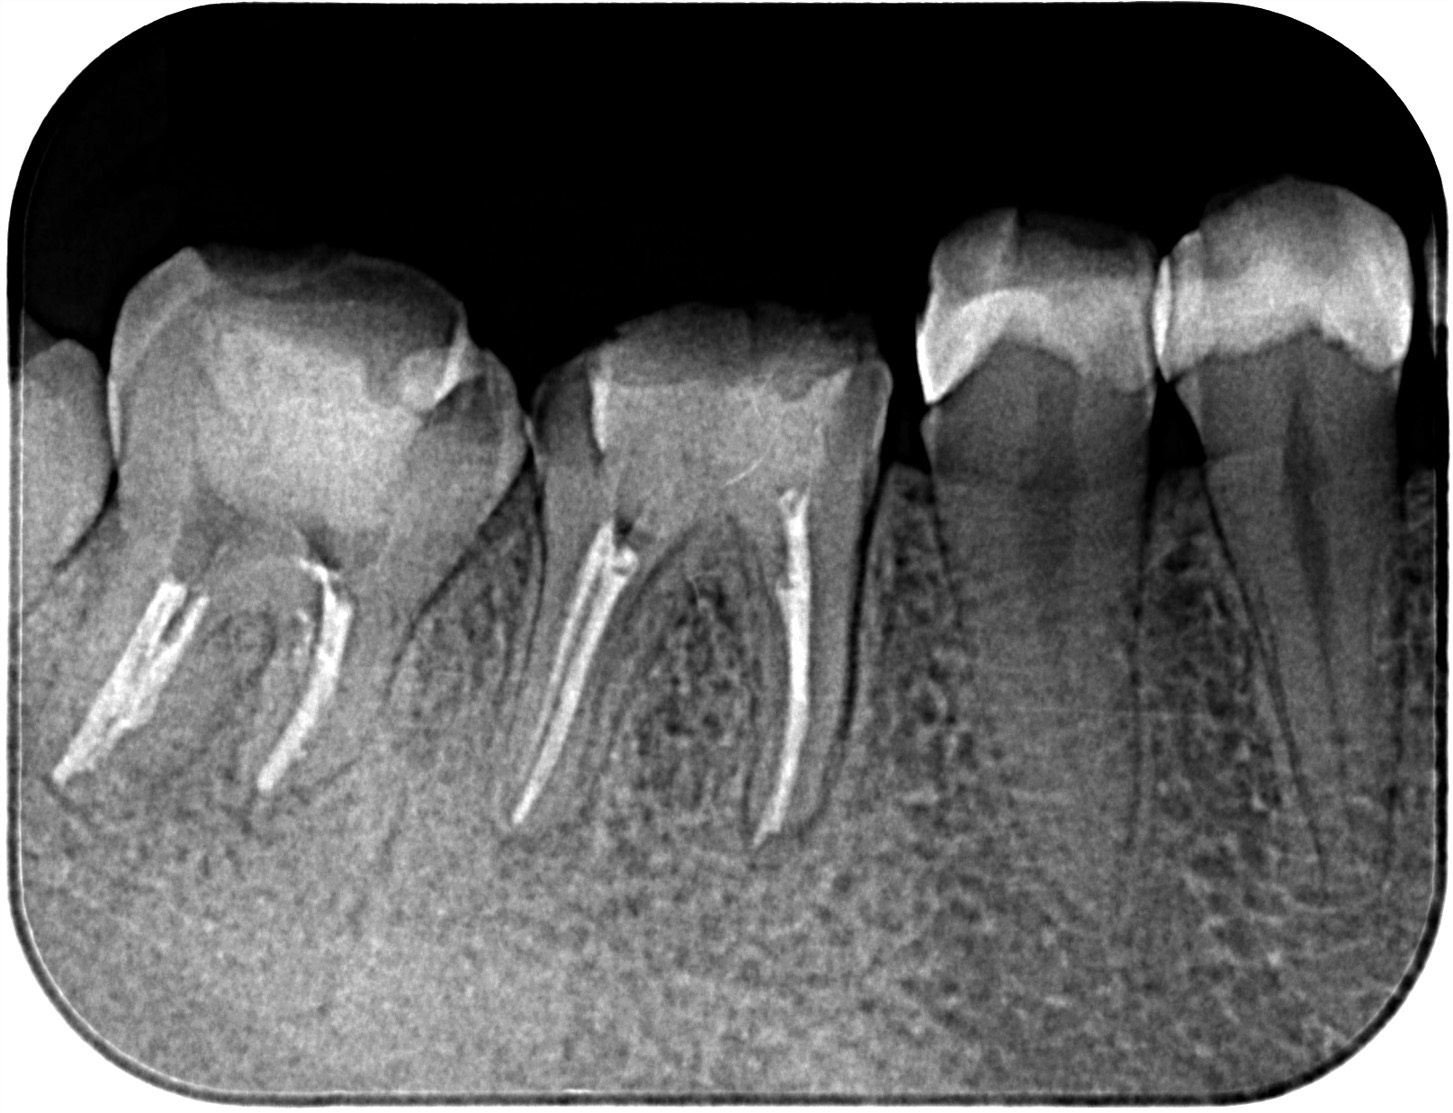

| 診断結果 | 右下7番歯根破折 |

| 治療内容 | 抜歯即時インプラント |